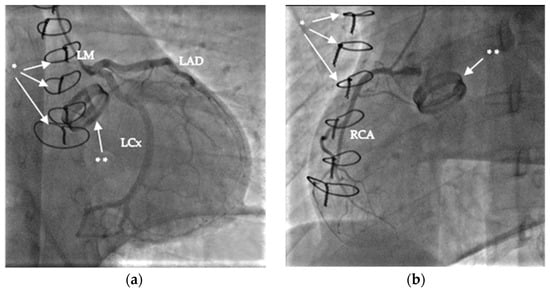

| 19:34 | immediate coronary angiogram, negative result | |